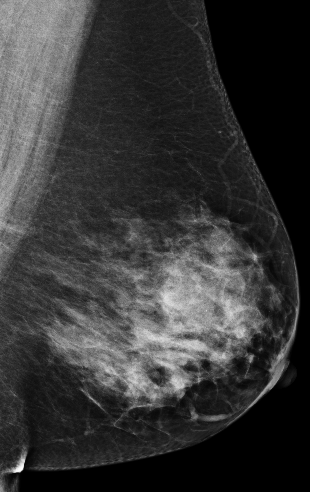

Masking refers to the phenomenon in which a tumor is hidden by the surrounding breast tissue, causing the cancer to be difficult or even impossible to discern with regular mammography, as seen in Figure 2. Masking can also result in large invasive cancers111We define large invasive cancers as those confirmed to have spread and be 2cm at time of diagnosis. – a small cancer may be difficult to discern in certain images, allowing it to grow to a more lethal size. Masking is correlated with breast density, as it has been shown that cancer in dense breasts is more likely to be missed during screening [5, 6, 7]. Density can be subjectively assessed by radiologists via the BI-RADS density standard (ACR) [8, 9], or measured by automated tools such as Libra [10]. These density measurements, however, do not perfectly correlate with masking potential. Radiologists consider the distribution and pattern of tissue when assessing masking potential, and have called for automated methods to assess the masking effect [11]. Until now, the question of exactly how masking potential should be quantified remains an open one, although some subjective notion has been added to certain categories of the most recent edition of BI-RADS density [12].

| Large invasive cancer | Same cancer, likely masked | Tumor size & frequency | |

CSAW-M consists of screening mammograms along with metadata describing expert masking potential assessments, clinical endpoints, density measures, and image acquisition parameters. CSAW-M is part of an ecosystem of mammography datasets based on the CSAW population-based cohort [25], depicted in Figure 2. CSAW is a collection of millions of screening mammograms of screening participants aged 40 to 74 gathered from the three breast centers of the Stockholm region between 2008 and 2015. The CSAW case-control dataset, hereafter referred to as CSAW for brevity, is a subset of the full CSAW cohort containing all cancers, along with a random sampling of healthy screens from the Karolinska breast center. A portion of CSAW (2,580 screening participants) is designated as a private held-out test set, unavailable to the public, for controlled benchmarking of various tasks. CSAW-M is subset of CSAW, created here, to study masking. It is divided into a training set (9,523 examples), a public test set (497 examples), and a private test set corresponding to those in CSAW (475 examples). A summary of the dataset is provided in Table 2. CSAW-M partially overlaps with CSAW-S, a sister dataset focused on segmentation in mammograms [24]. Below, we describe the procedure followed to create CSAW-M depicted in Figure 3.